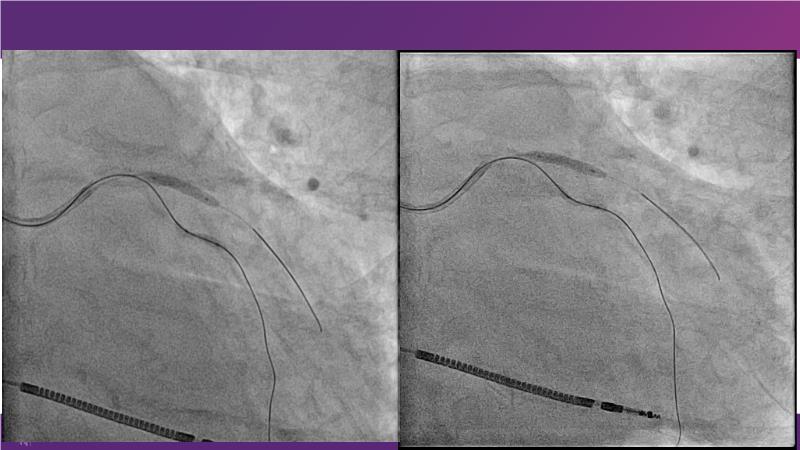

With this session, keep up to date on the evidence, trials and outcome data for intravascular lithotripsy in severely calcified lesions. Learn how to use this technique in real-world patients and understand its role in the treatment algorithm for severely calcified coronary lesions.

- To learn how to use intravascular lithotripsy in real-world patients with severely calcified coronary lesions

- To understand the appropriate role of intravascular lithotripsy in the treatment algorithm for severely calcified lesions